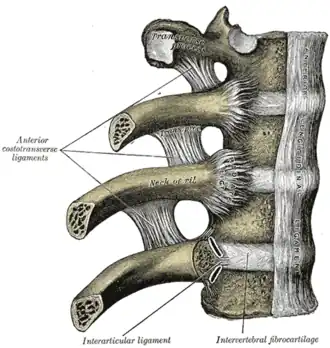

Costovertebral articulations. Anterior view.

Costovertebral articulations. Anterior view. -